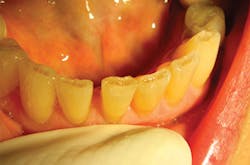

The noncontact technique enables restoration of delicate areas, such as worn incisal edges of lower anteriors, which often absorb stain over time and cause cosmetic concerns for many patients. The lack of collateral damage when using a laser (unlike the microfractures created by the vibration of a drill), and the ability to create convergence toward the incisal simply by changing angulation of the laser tip from buccal to lingual, provide both macro- and microretention, and hence, the longevity of these restorations (figures 5a and 5b).

Figures 5a and 5b: Class VI anterior incisal attrition restoration